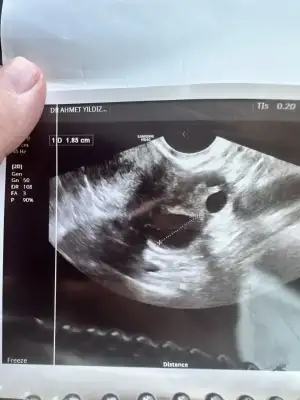

Merhaba kızlar bugün doktor muyanem vardı rahmime baltı yumurtan çatlamiş dedi döllenme var mı yok mu bir şey söylemdi rahmin kalınlaşmış dedi anlayan varsa bakabilir mi rica etsem 🥹